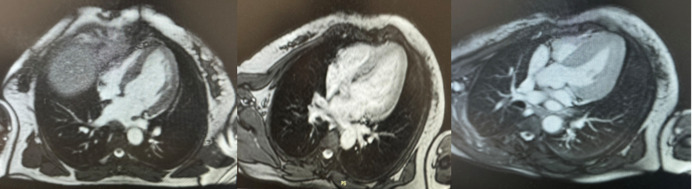

Takotsubo心肌病通常由继发于各种应激因素的严重肾上腺素能激增引发。在罕见的情况下,过量的儿茶酚胺分泌由于嗜铬细胞瘤可能是原因。典型表现为左心室尖部运动障碍。在这个病例报告中,我们描述了一个不典型的takotsubo心肌病病例,其特征是左心室下壁顶端和中间段运动不足,导致发现潜在的嗜铬细胞瘤。虽然这种关联是罕见的,但考虑它是至关重要的,特别是在非典型的形式,因为一旦肿瘤被切除,这种现象是可逆的。

Takotsubo cardiomyopathy is typically triggered by severe adrenergic surges secondary to various stress factors. In rare cases, excessive catecholamine secretion due to a pheochromocytoma may be the cause. It is typically manifested by dyskinesia of the apex of the left ventricle. In this case report, we describe an atypical case of takotsubo cardiomyopathy, characterized by hypokinesia of the apical and mid-segments of the inferior wall of the left ventricle, which led to the discovery of an underlying pheochromocytoma. Although this association is rare, it is crucial to consider it, especially in atypical forms, as once the tumor is resected, the phenomenon becomes reversible.